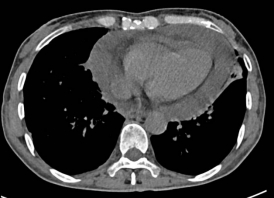

近日,一位肿瘤晚期的老年女性患者因并发急性心包填塞,被紧急送往广元市第一人民医院心胸血管外科就诊。入院时,患者已出现严重呼吸困难、心力衰竭等症状,剧烈的胸闷与濒死感让她痛苦不堪。检查显示,肿瘤转移引发的大量心包积液已对心脏形成致命压迫,若不及时解除压迫,患者随时可能因心跳骤停死亡,生命危在旦夕。

手术当天,陈均团队与麻醉科紧密协作。麻醉科张莉副主任、刘兴红医师在超声引导下精准区域神经阻滞,配合短效镇静镇痛药物,确保患者在自主呼吸状态下平稳接受手术。术中,陈均团队通过单孔胸腔镜精准定位心包积液区域,仅以微小切口完成开窗引流操作,快速排出压迫心脏的积液,成功解除了致命性心脏压迫。整个手术过程视野清晰、操作精准高效,在最大限度保障患者安全的同时,将手术创伤降至最低。